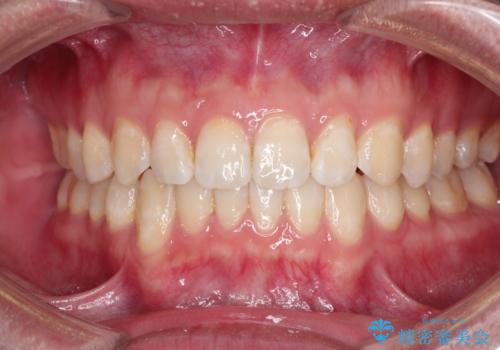

前歯がガタガタ インビザラインによる矯正

下の奥歯を後方へ移動させてスペースを確保して、前歯を並べる計画としました。

目立たない装置をご希望されたので、インビザラインにて矯正治療を行いました。

使用時間を守っていただけたので、比較的スムーズに矯正を終了することができました。